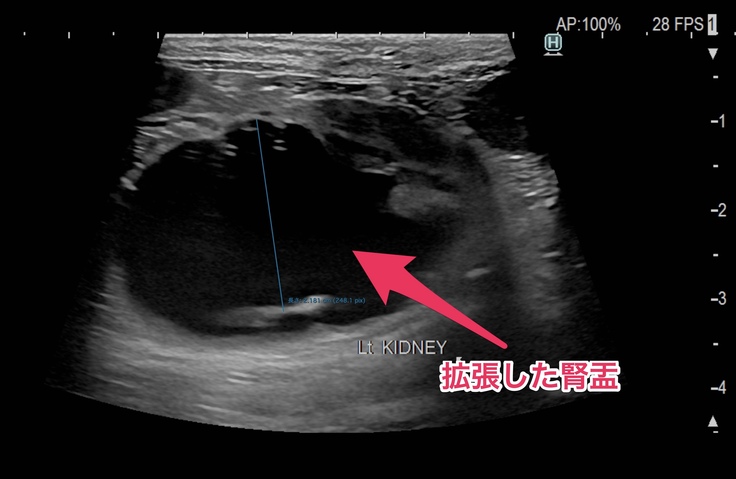

🐈左の腎盂。黒い影がぱんぱんに膨らんでいます🐈

今は右側の腎臓と腎盂機能が正常で、機能していない左側の腎臓の分までカバーしてくれているので血液検査でも異常な数値は出なかったけど、右の方も左側と同じように詰まってしまえば腎臓の機能がストップしてしまうので尿毒症や腎不全になったりして食欲不振や嘔吐するようになって体調が良くない日が多くなったり、透析等の別の治療が必要になる場合もあるかなと説明を受けました。